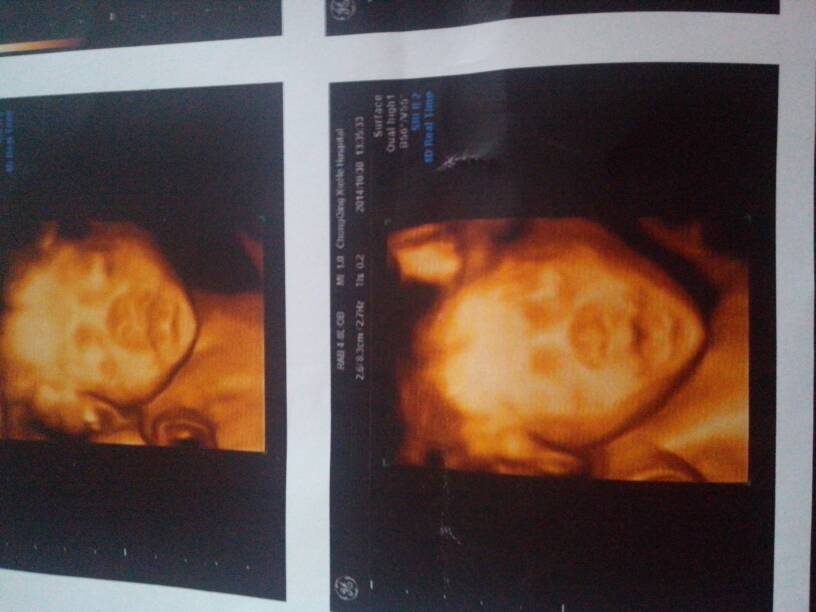

双顶经:61mm 头围:217mm 腹围:199mm 股骨长:43mm 肱骨长:40mm 胎心率:142次/分。帮忙看下男宝女宝

你好,胎儿的大小相当于24周左右的,胎心率在正常范围的,但是性别是不能确定的,按时产检。,祝你生一个健康的宝宝啊